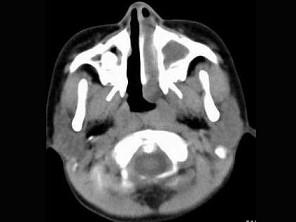

问题 男,7岁,无意发现鼻腔肿物,无明显症状,CT如图所示,最可能诊断为 ( )

选项 A、鼻乳头状瘤 B、鼻炎及副鼻窦粘膜下囊肿 C、鼻炎 D、鼻炎鼻息肉 E、鼻淋巴瘤

答案 D